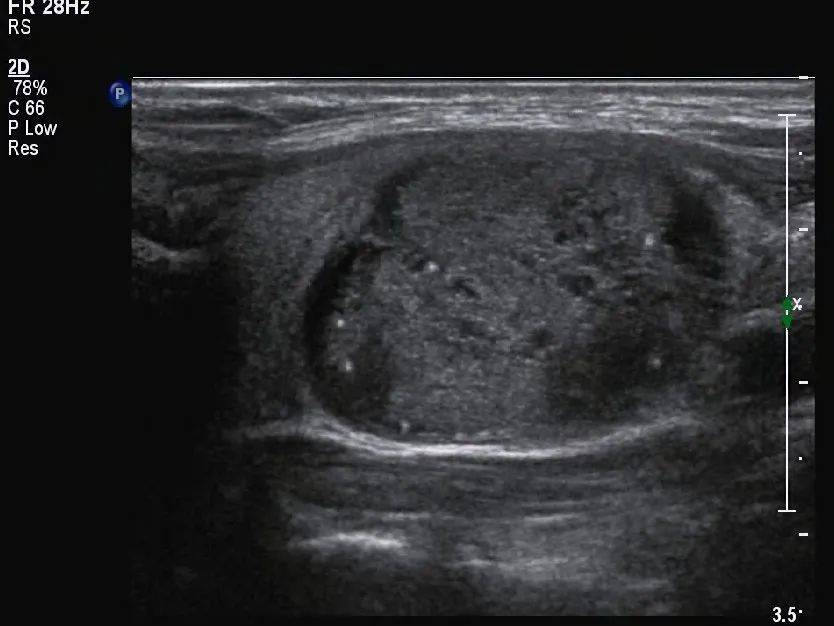

病例回顾 李某,女, 39 岁,因自觉颈部不适就诊,行甲状腺超声检查。 超声所见 甲状腺形态失常,左侧叶增大,内部回声不均匀,见囊实混合性结节,大小约 33mm×19mm×28mm ,形态规则,边界清